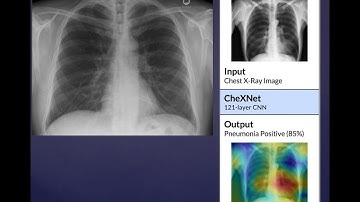

DD_Machine Learning Algorithm Diagnose Pneumonia | CheXnet